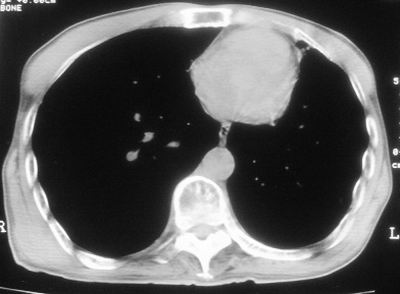

标题: CT11864:男,47岁,反复咳嗽、咯痰、咯血3年,请分析. [打印本页]

标题: CT11864:男,47岁,反复咳嗽、咯痰、咯血3年,请分析.

患者,男,47岁,反复咳嗽、咯痰、咯血3年,再发5天。痰培养未找到真菌、抗酸杆菌、癌细胞。

左肺上叶体积明显缩小,其内见多发透光区,纵隔向左侧移位,左肺下叶多发班片状病灶,边界模糊,1左肺上叶先天肺发育不全,2左肺下叶肺炎,

左肺上叶结核伴肺纤维化,纵隔移位,左肺下叶感染性病变,建议抗炎抗结核后复查,双肺气肿.

以下是引用xulianj在2008-2-25 21:01:00的发言:[br]左肺上叶结核伴肺纤维化有霉菌球形成,纵隔移位,左肺下叶感染性病变,建议抗炎抗结核后复查,双肺气肿.

考虑:左肺慢纤伴霉菌球形成、双肺全小叶型肺气肿。

1)考虑为:左肺上叶肺结核(空洞形成),伴左下肺感染;不排除霉菌感染可能。2)肺气肿。

左肺上叶结核伴肺纤维化空洞形成并左肺下叶感染,纵隔牵拉移位,建议作进一步检查排除左侧肺霉菌感染可能。